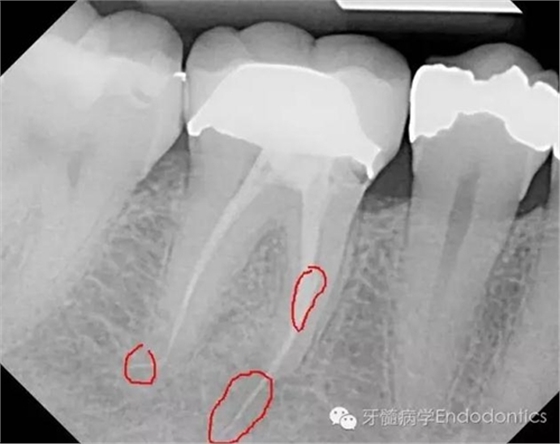

患者因右下第一前磨牙劇烈疼痛、腫脹來診,自訴2年前該牙行根管治療,突發(fā)劇痛。X線示患牙已行根管治療并超填。患牙診斷為已行根管治療合并急性根尖周膿腫。一些牙醫(yī)和牙髓病??瓶赡軙苯硬扇「馐中g治療患牙,而我認為手術是最終手段,尤其對于該病例。

圖2.術前X線片(b)